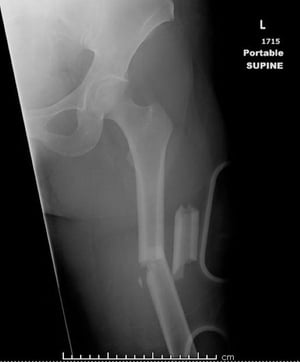

Frattura mediale della diafisi femorale (1)

Questa immagine mostra una frattura comminuta, angolata e accorciata mediale della diafisi femorale.

Image courtesy of Danielle Campagne, MD.